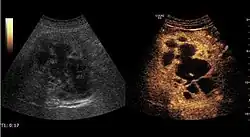

The ultrasound appearance is a well defined lesion, with very thin, almost unapparent walls, without circulatory signal at Doppler or CEUS investigation. The content is transonic suggesting fluid composition. The presence of membranes, abundant sediment or cysts inside is suggestive for parasitic, hydatid nature. Posterior from the lesion the acoustic enhancement phenomenon is seen, which strengthens the suspicion of fluid mass. They typically displace normal liver vessels but no vascular or biliary invasion occurs.

-

Liver cyst -

Hydatid liver cyst. Diagnostic criteria are the presence of membranes and sediment inside.